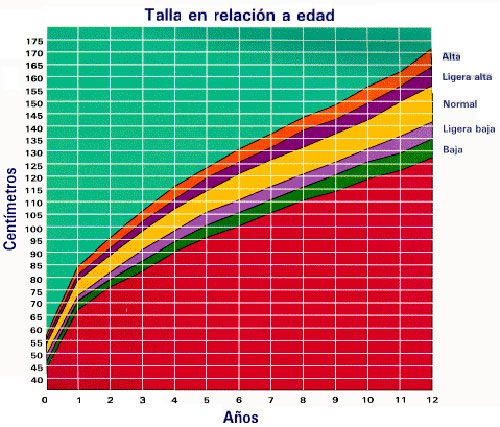

Mostramos una tabla en la que se refiere el concepto de normalidad para una persona de 1,53 cm, pero a los 12 años.

El escaso desarrollo corporal que se observa (1,53 cm de estatura y 38 kg de peso) a pesar de haber terminado de erupcionar su dentición permanente, nos obliga a posponer el tratamiento y se le cita al año siguiente.

Se mantiene su estatura en 1,53 cm y su peso persiste en 38 kg.

En el año 2012 decidimos operar a pesar de tener frente a nosotros a una persona de 22 años con una estructura corporal de 12 años.